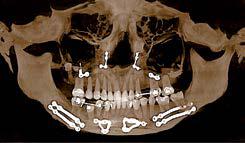

Nell’ambito della radiologia 3D ortopedica, il centro diagnostico utilizza il nuovissimo macchinario NewTom 5G XL, in grado di individuare con la massima precisione la presenza di fratture o lussazioni delle articolazioni, controllare la corretta guarigione di una frattura, valutare una lesione o una ferita causata da infezione, artrite o crescita anormale dell’osso.

Il tutto mediante una semplice e veloce scansione, grazie alla quale si otterranno diverse immagini in 3D ad altissima risoluzione e, per ottenere immagini ancora più nitide mediante un bassissimo dosaggio di radiazioni, gli esperti si avvalgono dell’innovazione racchiusa nella tecnologia Cone Beam.

Se con la radiologia tradizionale era necessario eseguire scansioni multiple, la novità introdotta dal macchinario NewTom 5G XL risiede nella capacità di fornire immagini ad alta risoluzione in un’unica scansione, mostrando nitidamente i dettagli delle articolazioni degli arti superiori e inferiori. Inoltre, a differenza della tecnologia 2D, la radiologia 3D ortopedica permette di individuare immediatamente alcune patologie come quella del metatarso, la quale richiede un allineamento visivo dedicato o una diagnosi delle micro fratture ossee.